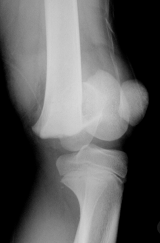

LES FRACTURES DU FEMUR |

Les

fractures de la diaphyse du fémur (partie longue de l'os) sont

fréquentes. |